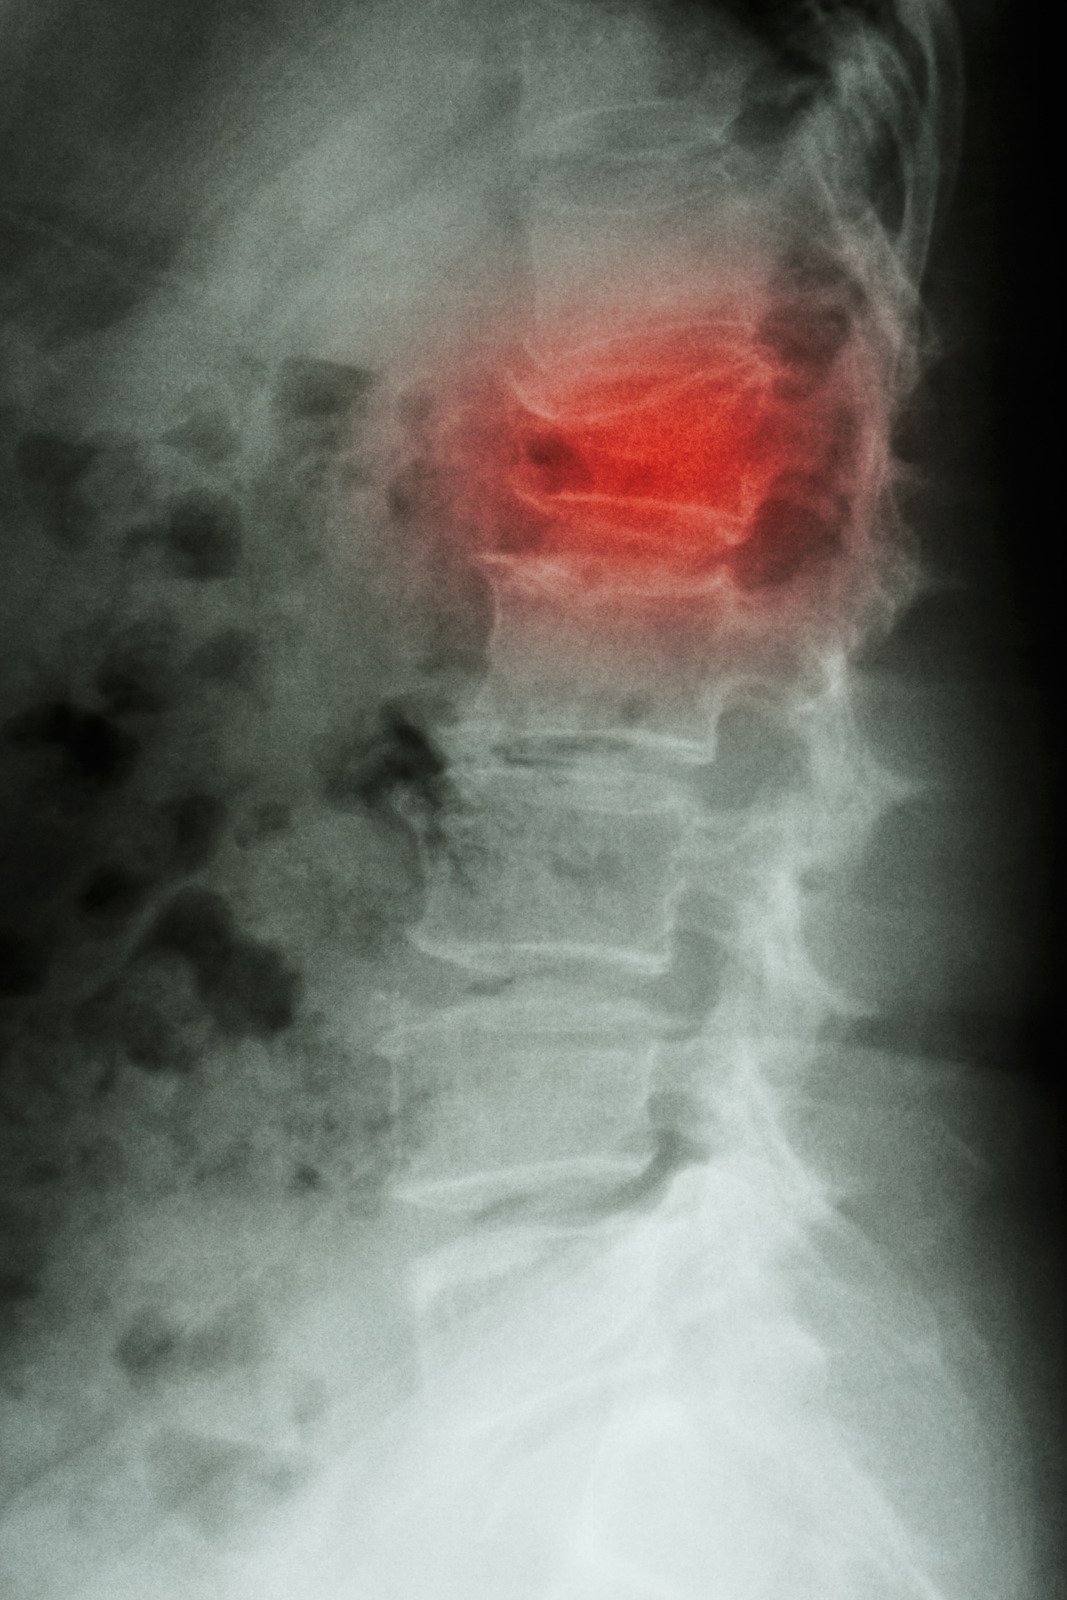

영상 진단

X-레이: 척추의 골절 여부를 확인하고, 골절의 위치와 유형을 평가합니다. X-레이는 뼈의 이상을 빠르게 파악할 수 있는 가장 기본적인 검사 방법입니다.

CT 스캔: 더욱 상세한 이미지를 제공하여, 골절의 정확한 위치와 복잡한 골절 패턴을 확인할 수 있습니다. X-레이로는 파악하기 어려운 세부 사항을 확인하는 데 유용합니다.

MRI: 연조직, 신경, 척수와 같은 구조물의 손상을 평가하는 데 필요합니다. MRI는 신경 압박이나 척수 손상의 여부를 확인하는 데 특히 중요합니다.